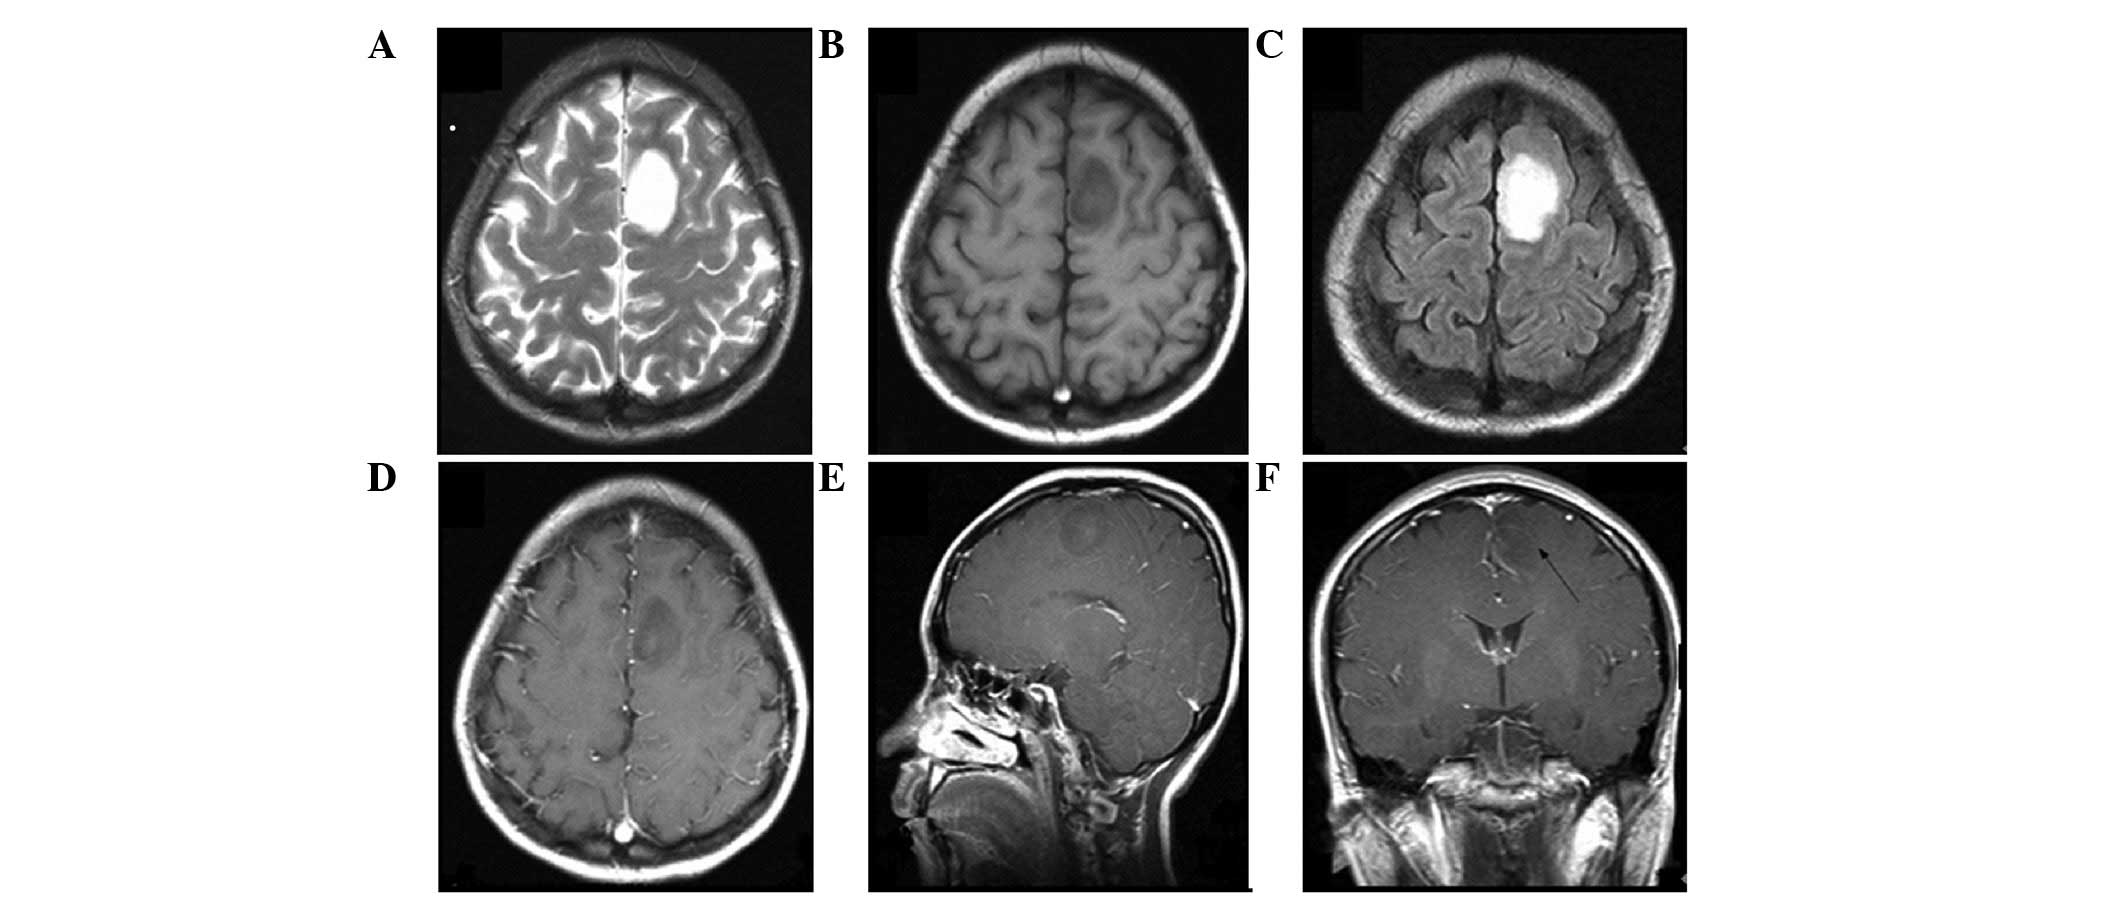

Figure 3

Patient with histological World Health Organization grade III anaplastic astrocytoma and no isocitrate dehydrogenase 1/2 mutation. Magnetic resonance imaging (A) T2-weighted, (B) T1-weighted and (C) postcontrast T1-weighted axial as well as post-contrast T1-weighted (D) sagittal and (E and F) coronal images demonstrated an ill-defined mass severely invading the medulla oblongata (high-risk region). The lesion showed heterogeneous T2 hyperintense and T1 iso-hyperintense signals with apparent enhancement following the contrast administration and a significant mass effect was observed without edema.